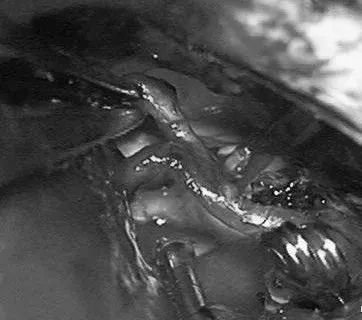

(a)侧位(b)前后位].(c)他取侧卧位,右侧朝下,鼻朝下,中线取水平位以便靠重力牵拉右侧枕叶。窦汇开颅,显露SSS、TrvS、枕较、后纵裂和镰幕交界处。SplenA沿胼胝体压部上升,顺着它可达AVM(续)。